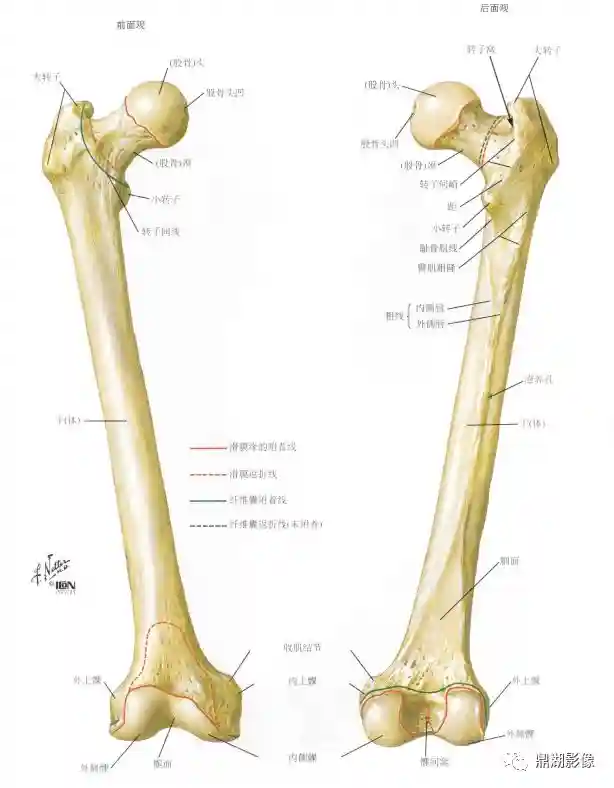

股骨

人体最长最结实的长骨,分为一体两端,上端有朝向内上的股骨头,头下外侧的狭细部为股骨颈

下端有两个向后突出的膨大,为内侧髁和外侧髁,两髁之间的深窝为髁间窝,两髁侧面最突起处,分别为内上髁和外上髁